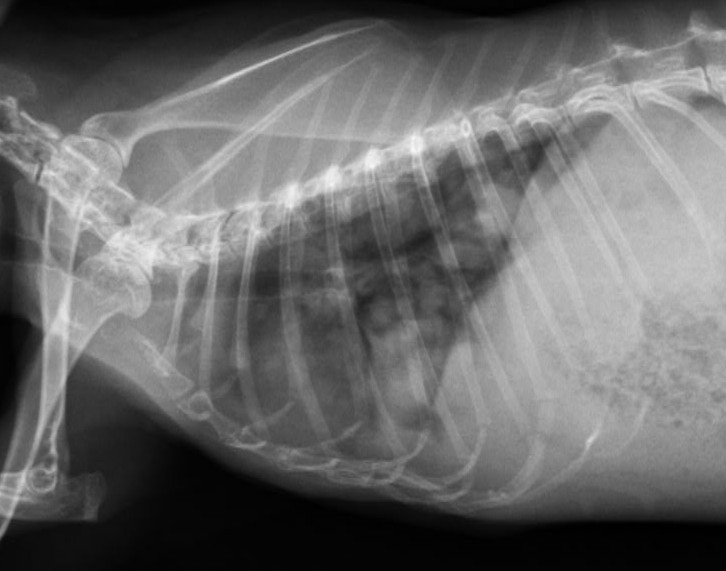

診断は問診と身体検査に加え、画像検査によって行います。腹部触診で子宮の腫大を疑うことがありますが、確定には腹部超音波検査が有用です。超音波検査では子宮壁の肥厚、内部構造の不整、液体貯留の有無を確認します。必要に応じてX線検査で転移の評価を行い、血液検査により全身状態を把握します。